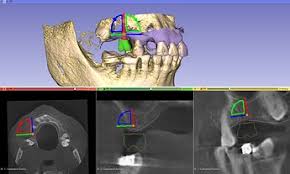

3D Slicer Surgery: Virtual Planning Made Easy Surgical simulation in 3D Slicer feels a bit like playing a game — just with real anatomy. I

3D Slicer Implantology: Plan Smarter Planning implants digitally sounds fancy, but honestly it’s become the norm. I remember trying 3D Slicer for the first time